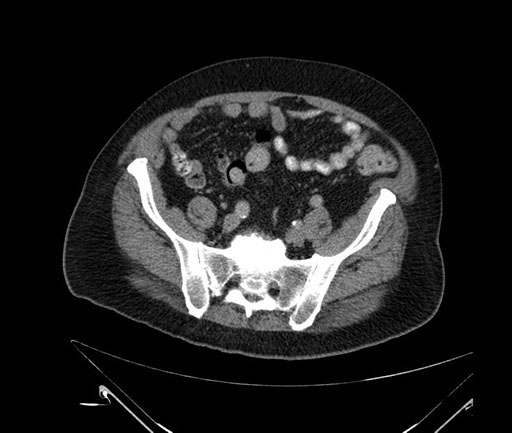

Axial - stented